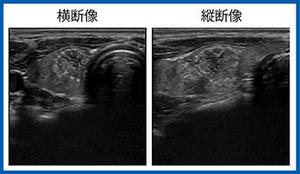

日本乳腺甲状腺超音波医学会第1回春季大会ランチョンセミナー1 乳房超音波検査の対策型検診に向けた精度管理の重要性

(2024年8月号)

対策型 乳房超音波検診が始まる かもしれない ─どんな機種,どんな機材なら大丈夫?

須田 波子(愛知乳がん検診研究会)